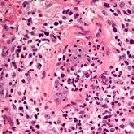

GPA

GPA staat voor Granulomatose met Polyangiitis en werd voorheen de ziekte van Wegener genoemd.

Het is een Primaire (onbekende oorzaak) Systemische (het gehele lichaam kan zijn aangedaan) Vasculitis (ontstekingen van de binnenwanden van de kleine bloedvaten).